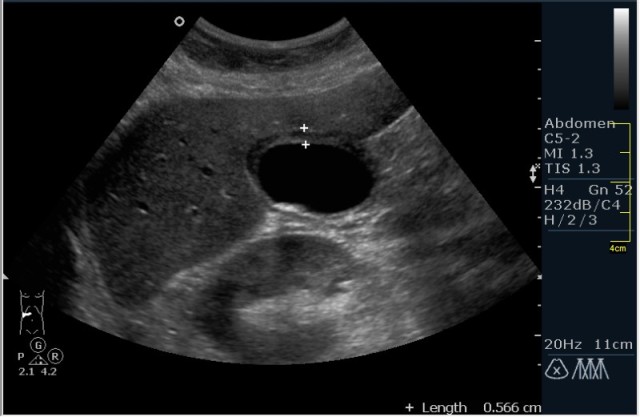

Пациент с болями в эпигастрии

Диагноз не сложен. Как вы думаете, что необходимо рекоммендовать именно при такой картинке?

острый калькулезный холецистит

Без сомнений, вопрос касался рекоммендации. При таких множественных мелких конкрементах, желательно выполнение интра-операционной холангиографии, для исключения наличия конкрементов общего жёлчного протока.